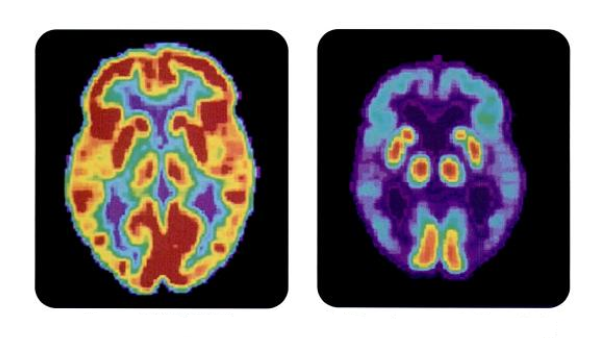

V možganih oseb z Alzheimerjevo boleznijo našli bakterijo

Mednarodna raziskovalna skupina je v možganskem tkivu oseb, obolelih za Alzheimerjevo boleznijo, odkrila prisotnost bakterije Porphyromonas gingivalis. Omenjena bakterija se sicer pretežno nahaja v človeških ustih, kjer lahko povzroča kronično vnetje dlesni oziroma parodontozo. Raziskovalke in raziskovalci so našli dokaze, da bakterija v možganih povzroča razvoj Alzheimerjeve bolezni, osnovali pa so tudi potencialno zdravilo, ki uspešno zdravi okužbo z omenjeno bakterijo v mišjih možganih.

Znanstvenice in znanstveniki so potrdili sum, da se omenjena bakterija nahaja v možganskem tkivu oseb, ki so imele Alzheimerjevo bolezen. Glavni simptomi te napredujoče možganske motnje so težave pri spominu in mišljenju. Eden od vzrokov za nastanek bolezni je tvorba nevrofibrilarnih pentelj. Glavna komponenta nevrofibrilarnih pentelj je protein tau, sestavni del struktur, ki živčnim celicam dajejo obliko in posledično sposobnost delovanja. Pri obolelih pa se zaradi tvorbe nevrofibrilarnih pentelj strukture možganskih celic podrejo.